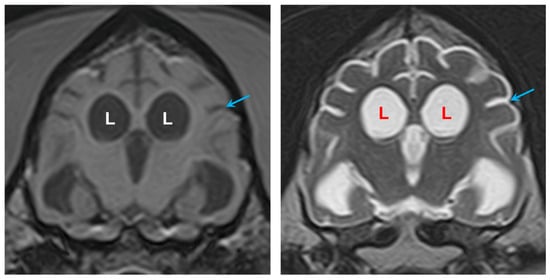

3.1. Disease Phenotype